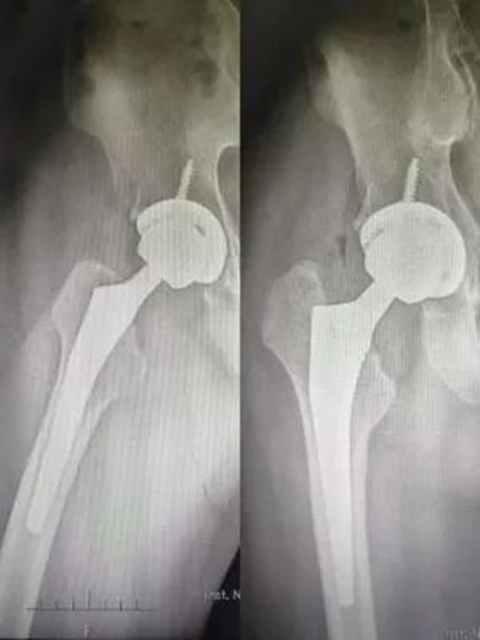

蒋先生术后1天开始下地行走功能锻炼

蒋先生术后X片

“我因为激素使用不当导致了双侧的股骨头坏死,后期肯定还会实施左侧的髋关节置换术。入院后,李主任就告知我人工关节集采降价的好消息,原本单侧的假体费用要4万多,现在只要8000元左右,换双侧的话要节约将近8万块钱,经济负担一下子就轻了!真的特别感谢国家的好政策,感谢西南医大附院骨与关节外科的各位医护人员!”蒋先生激动地说。